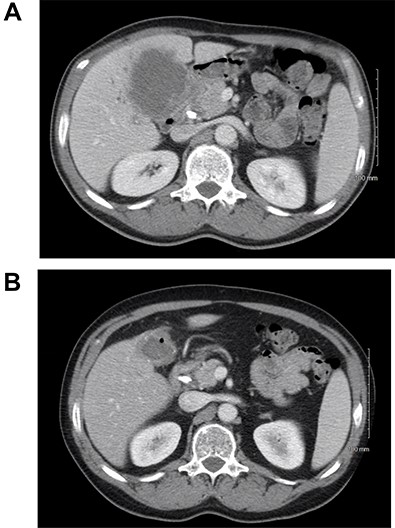

The patient received systemic chemotherapy with gemcitabine and cisplatin. After more than 2 months, he developed grade 3 neuropathy and experienced several episodes of cholangitis with liver abscess and bacteremia requiring multiple stent exchanges, and systemic therapy was discontinued. He then received trial-based immune check point inhibition with ipilimumab and nivolumab. There was good radiological (Fig. 1B) and tumor marker response (CA 19–9 7.05 U/ml). Immunotherapy had to be stopped after 10 months due to grade 3 autoimmune hepatitis. He was treated with oral steroids and immunosuppression with mycophenolate mofetil, resulting in the normalization of liver function tests. A R0 resection was now deemed a possibility, with a goal of best tumor control and long-term biliary decompression. He underwent right portal vein embolization after which his left lobe future liver remnant grew from 28 to 45% at a kinetic growth rate of 5.6% per week (Fig. 2). He underwent extended right hepatectomy with radical cholecystectomy, portal and hepatic artery lymph node dissection, and Roux-Y hepaticojejunostomy biliary reconstruction (Fig. 3). Pathology examination revealed a 6.5-cm gallbladder and hepatic tissue mass with xanthogranulomatous inflammation and nodular fibrosis, without residual viable tumor, margins free of carcinoma and 0/17 lymph nodes involved, consistent with an ypT0N0M0 gallbladder cancer, R0 resection. After an initial postoperative surgical site infection, he has now fully recovered and is disease-free at 10-month follow-up.

CT scan image of the liver: (A) small left lobe prior to portal vein embolization; (B) left lobe hypertrophy after right portal vein embolization.